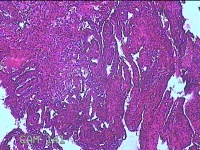

性别

女

年龄

32岁

临床诊断

1.异常子宫出血 2.轻度贫血 3.宫内节育器 4.慢性宫颈炎

一般病史

阴道流血1月余。

标本名称

宫颈内容物

大体所见

灰白暗红色不规则碎组织2.3x1.3x0.3cm一堆。

图1